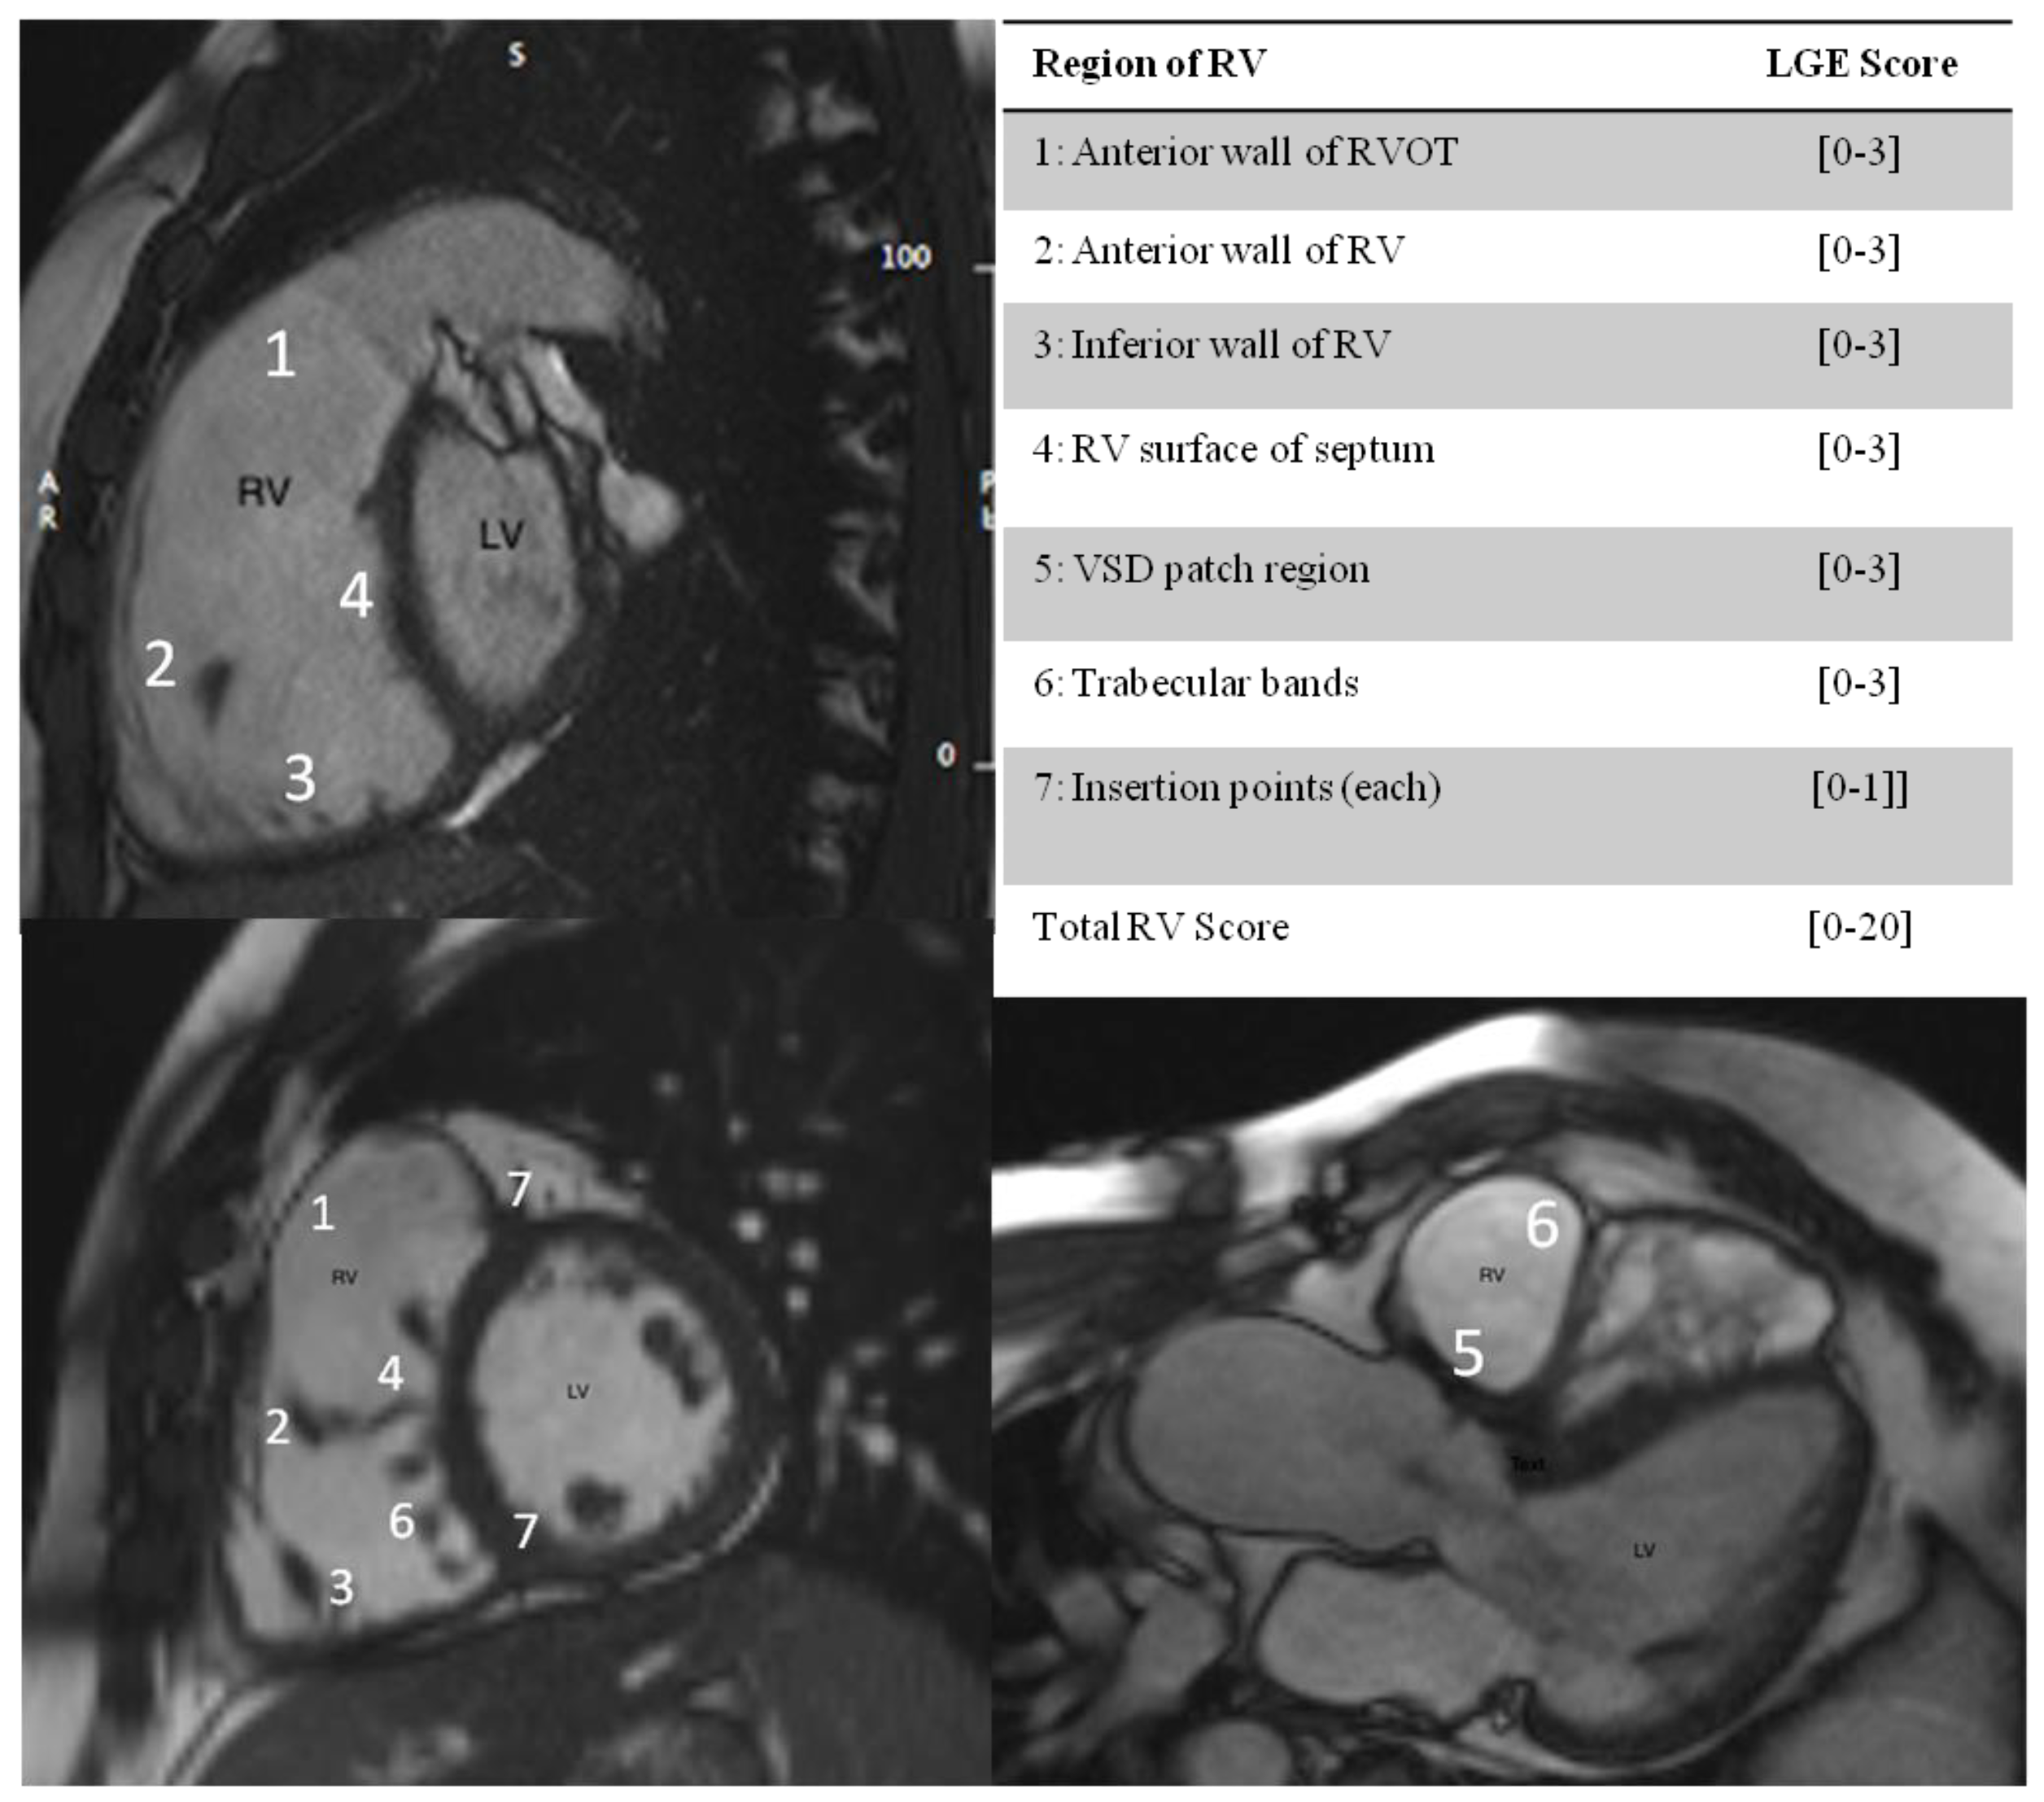

For the LGE RV analysis, a segmentation system of RV was utilized as previously described [14]. The RV was divided into 7 segments in slices aligned with the RV outflow tract, the LV outflow tract, and the LV-RV short axis. Segments of RV wall with LGE were scored according to the extent of enhanced myocardium, and expressed as a score out of 20 (Figure 1). Strain analysis: Using specialized software (Circle Cardiovascular Imaging Inc.) from the cine sequences in the longitudinal axis, the global longitudinal strain values for the left and right ventricles were calculated.

Figure 1.

Segmentation system for LGE RV analysis. 1–7: RV segments The division of the RV into 7 segments is shown in slices aligned with the RVOT, the LV outflow tract, and the LV short axis, with maximum LGE score per segment in brackets. [0,1,2,3]: LGE RV SCORE, 0: no linear extent of enhanced myocardium; 1: enhancement of 1 trabeculation; 2: enhancement of 2 to 4 trabeculations; 3: enhancement of more than 4 trabeculations. The insertion points of RV and LV (marked 7) were each scored 0 for absence and 1 for presence of LGE. The maximum score was 20.